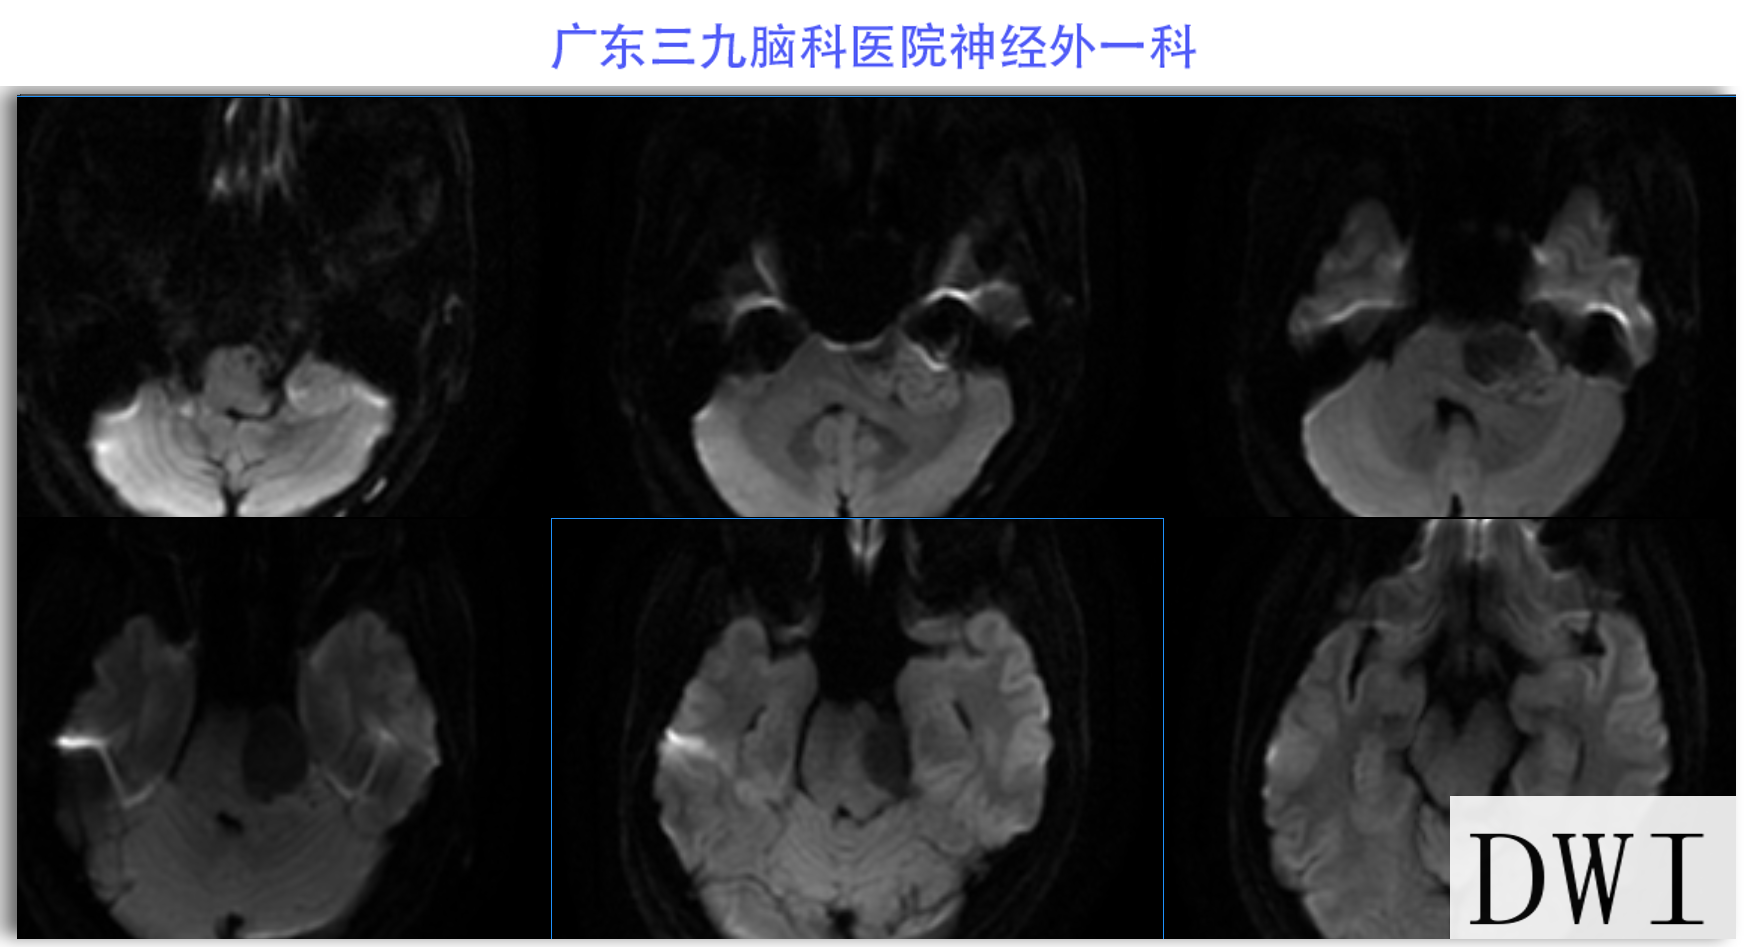

陈某某,女,41岁,因“左侧面部麻木3月余,吞咽困难半月余”于2024-02-17入院。患者3个月前出现左侧面部麻木,偶尔伴有头晕和左侧流泪,但没有听力下降或耳鸣。同时,患者也出现肢体乏力和行走不稳,但未接受任何治疗。半个月前,患者发现吞咽硬质食物稍有困难,同时左侧面部麻木加重。因此,前往当地医院就诊,并进行头颅MR检查,结果显示左侧CPA区存在占位性病变。为了进一步治疗,患者转诊至我院就医。术前检查显示:左侧角膜反射减弱,左侧鼻唇沟略微变浅,伸舌稍微右偏,咽反射迟钝。门诊诊断为“左侧巨大听神经瘤”,收治至我科进行住院治疗。手术过程顺利,术后患者恢复良好,面部轻度瘫痪与术前相同。术后病理检查结果确认为听神经瘤。